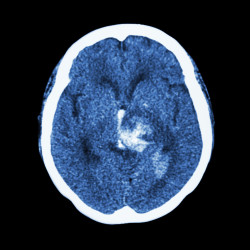

Pradaxa intracranial hemorrhageMany people taking Pradaxa may not be aware of the serious complications that can result from its use.

But for patients who experienced a Pradaxa intracranial hemorrhage, they may not be convinced that taking the medication was worth the risk.

This can lead to uncontrolled internal bleeding such as Pradaxa gastrointestinal bleeding or intracranial hemorrhage.

Pradaxa intracranial hemorrhage occurs when there is a bleed on the brain that may not be controllable.